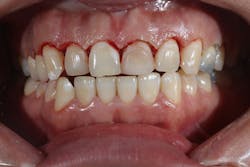

Figure 12: Pre-op clinical photo shows the discrepancies and disharmony of the gingival height. Incisions for esthetic crown lengthening on tooth No. 9 were done via the Er:YAG laser in contact mode (20 pps/60 mJ) to remove excess soft tissue in accordance with the pre-op probing depth measurements.

Figure 14: After osseous shaping and recontouring was done using the Er:YAG laser in contact mode (20 pps/80 mJ). All bony ledges and crestal bone were removed on teeth Nos. 9–11.

Figure 15: Immediate post-op of tissues repositioned into place. Simple interrupted sutures were used.

Figure 16: Two-year post-op shows gingival health and maintenance of gingival tissues.

The Er:YAG laser has been more recently known for its ability to remove calculus from a titanium implant surface as well as detoxification (figures 17–21).9 Many authors have shown the laser’s use in combination with mechanical debridement to be superior when using a regenerative approach to treat peri-implant diseases (figures 22–26).10 A particular feature of this laser is the microexplosions that occur when the laser energy is absorbed by water. The volume of these explosions suddenly expand up to 1,000 times, covering more surface area of a titanium implant. It has been found that both contaminated debris and the contaminated oxide layer are removed as a result of these microexplosions.11